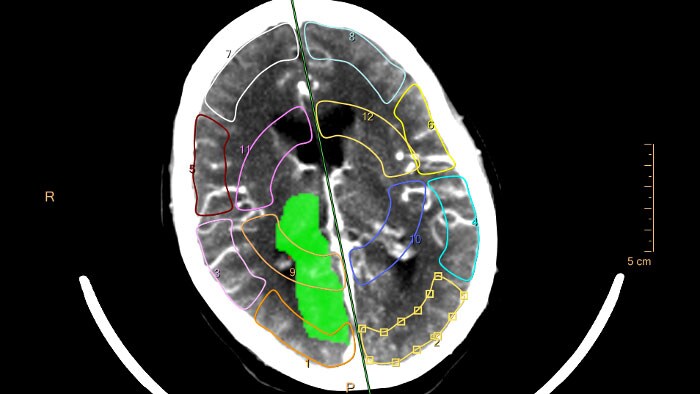

Optimice con inteligencia artificial

Fortalezca su departamento de radiología con inteligencia artificial

Escuche al Dr. M.A. van Buchem, presidente del departamento de radiología del Centro Médico Universitario de Leiden (LUMC), quien comparte sus perspectivas sobre la implementación de la inteligencia artificial (IA) en el ámbito de la salud para abordar los desafíos de los radiólogos. Philips AI Manager permite a sus radiólogos aprovechar aplicaciones de IA para realizar evaluaciones más completas y obtener profundos conocimientos clínicos sobre su flujo de trabajo radiológico.